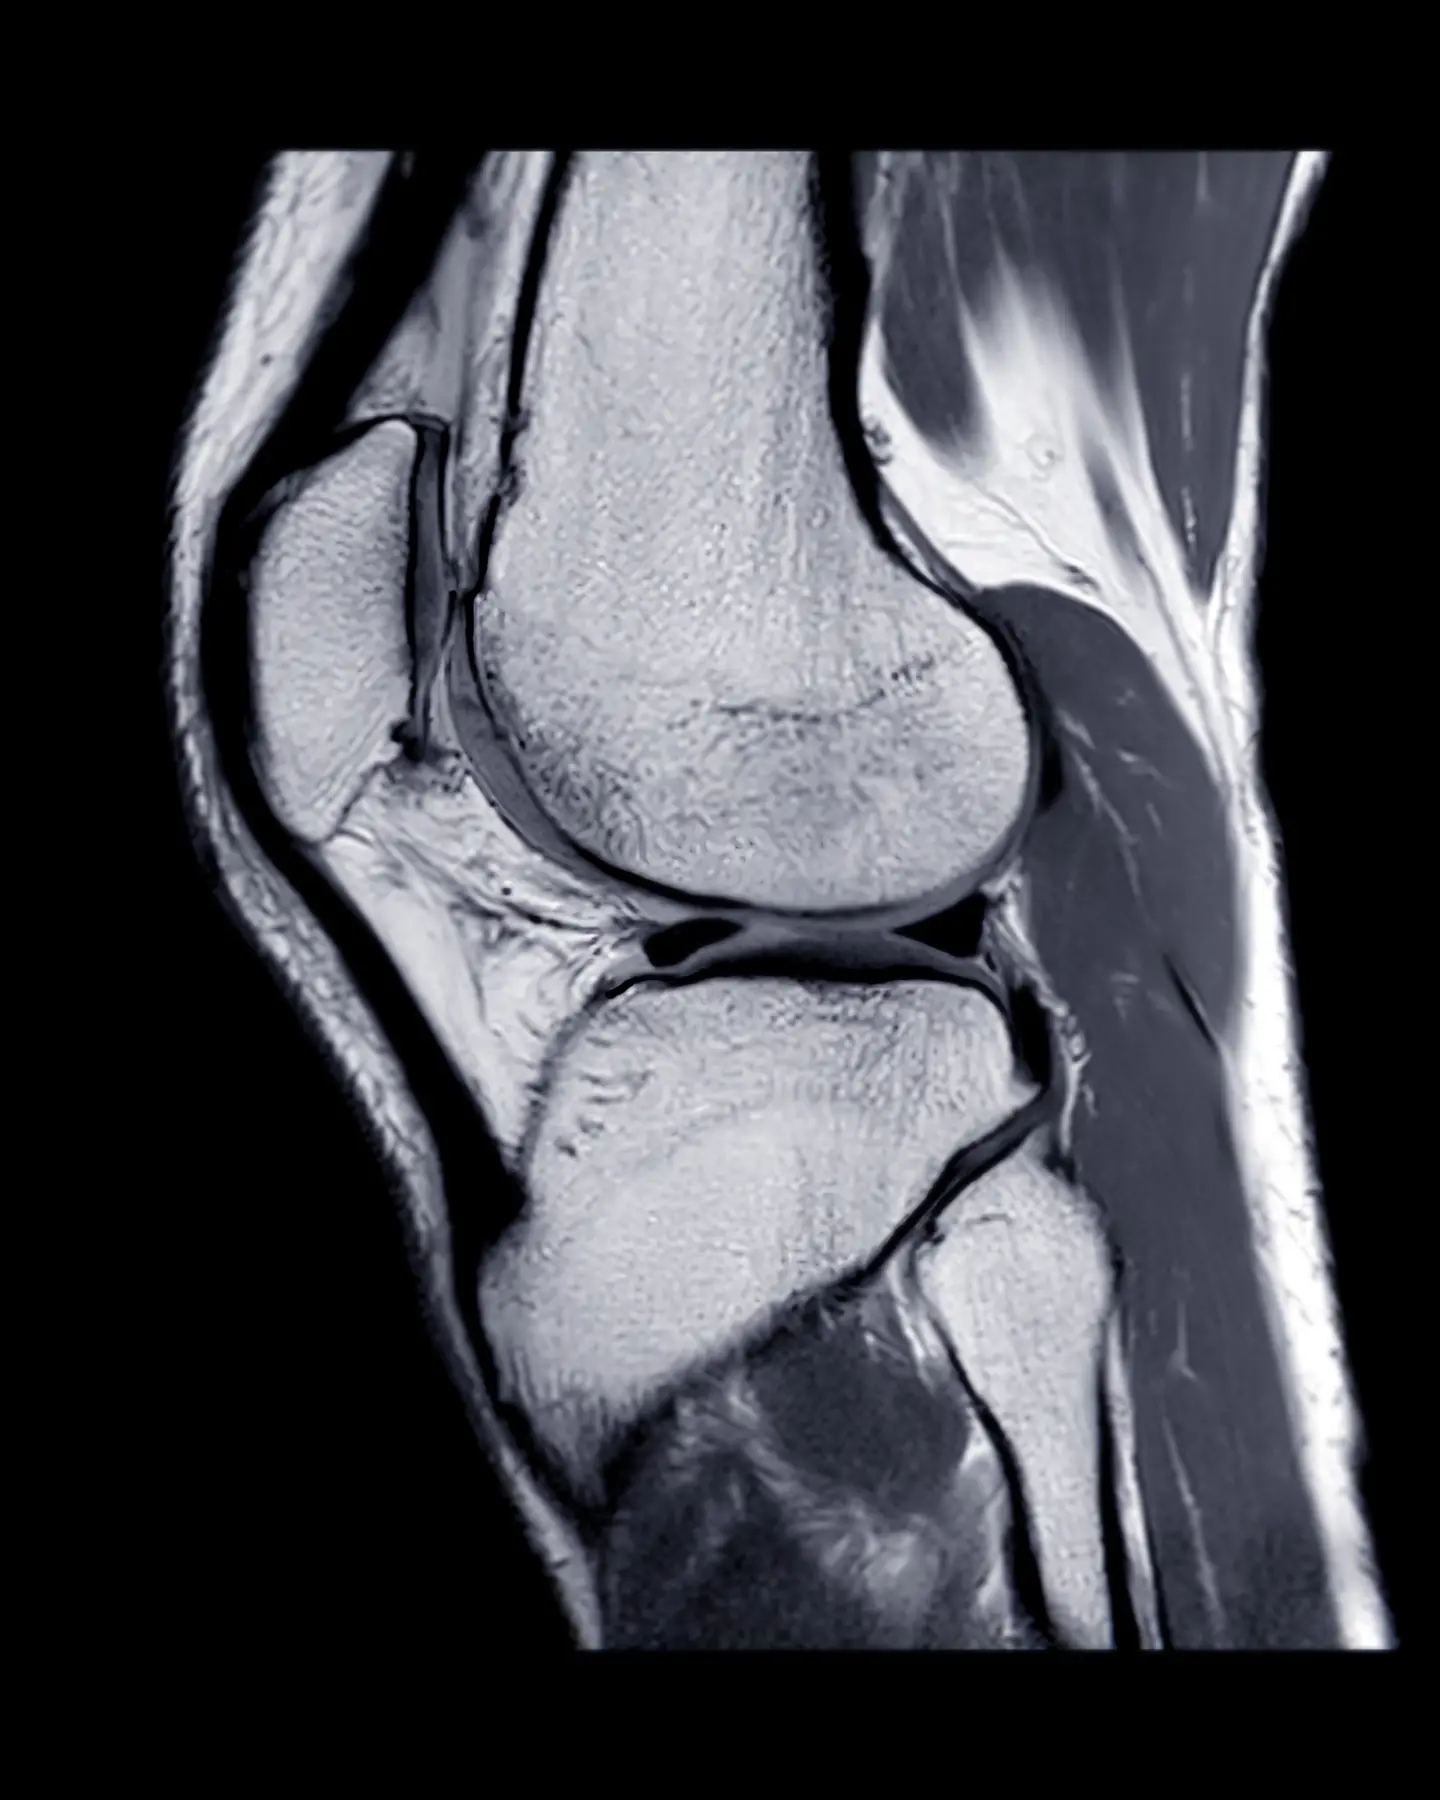

An MR arthrogram combines the use of MRI scanning with a contrast medium to examine the inside of a joint, such as a shoulder, knee, wrist or ankle, and to assess and diagnose injuries and other problems.

An MR arthrogram (an MRA) is a two-part MRI technique used to assess the condition of a joint.

The second part is an MRI scan of your joint to provide high contrast, cross-sectional images.

An MR arthrogram scan is used to diagnose and treat joint pain or joint injury related to the knee, shoulder, wrist, elbow, hip or ankle. It provides a clear image of the soft joint tissues.